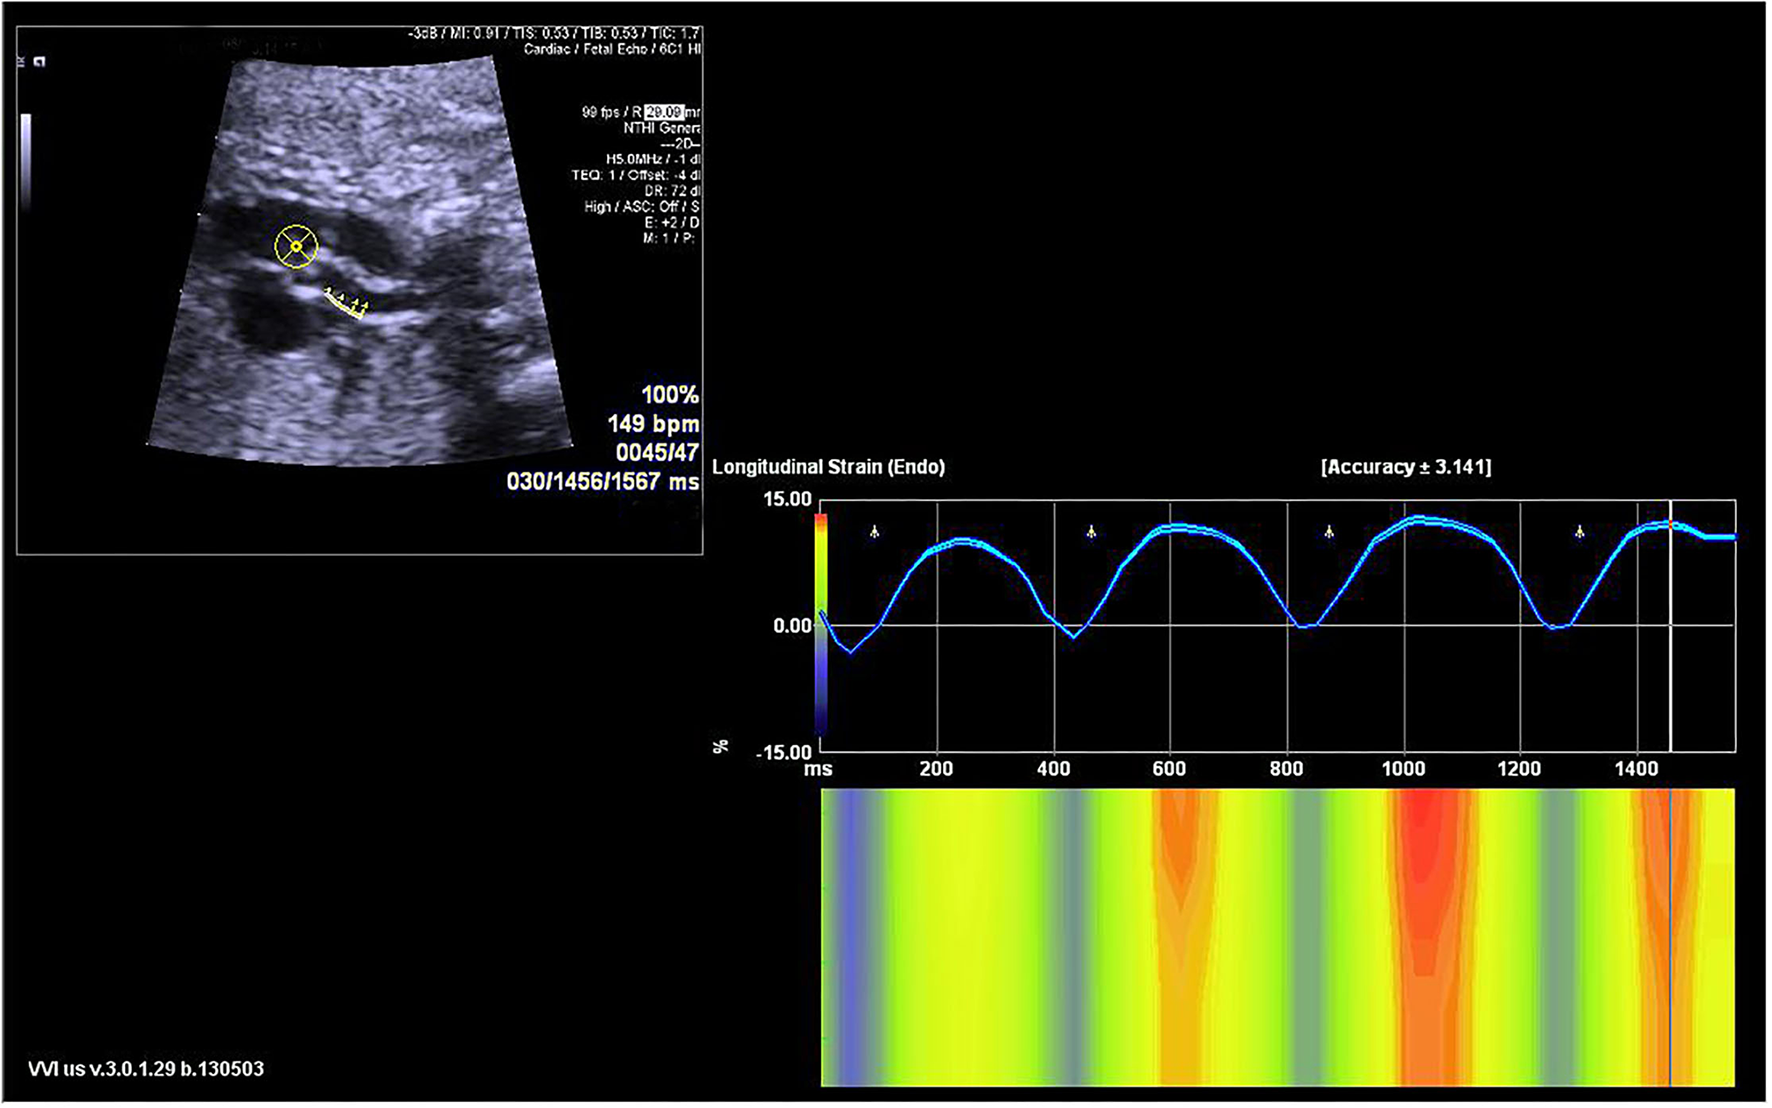

Figure 2

The velocity vector image of the traced posterior ascending aorta wall is shown in the sagittal view (left upper panel). The longitudinal strain curve of the traced wall was automatically calculated and displayed (right panel).

Fetal echocardiography was performed by one expert (ZS) who was blind to the fetal GA using an Acuson SC2000 system (Siemens Medical, WA, USA) with a 6C2 transducer. Standard multiple views of the fetal heart were obtained to evaluate the cardiac anatomy. Ascending aortic (AA) elastic properties were assessed using vector velocity imaging software (VVI; Siemens Medical, Solutions USA, Inc.). Global circumferential strain (GCS) of the ascending aorta was measured in the great artery short-axis view, while the mean longitudinal strain (MLS) of AA was evaluated in the left ventricle outflow tract (LVOT) sagittal view. First, the high-quality cine loop clips (36–54 frames/s) of the abovementioned views with at least 3 heart cycles were acquired and stored. Atrioventricular and semilunar valves needed to be clearly displayed to determine the cardiac phase in the follow-up analysis. Second, annularly tracing the AA along the blood-intima border in a still frame of short-axis view with optimal visualization was performed. The circumferential strain curve during the cardiac cycle was automatically calculated and displayed. GCS was recorded as the average of all segmental systolic peak circumferential strains (Figure 1). Third, the anterior and posterior walls of the AA were traced separately within the course between the sinotubular junction and the roof of the left atrium at the still frame of the LVOT view. Similarly, the longitudinal strain curve of the traced two walls was automatically displayed, and MLS was calculated as the mean systolic peak longitudinal strain of both the anterior and posterior AA walls (Figure 2). AA strains were measured three times, and the mean was used for statistical analyses.